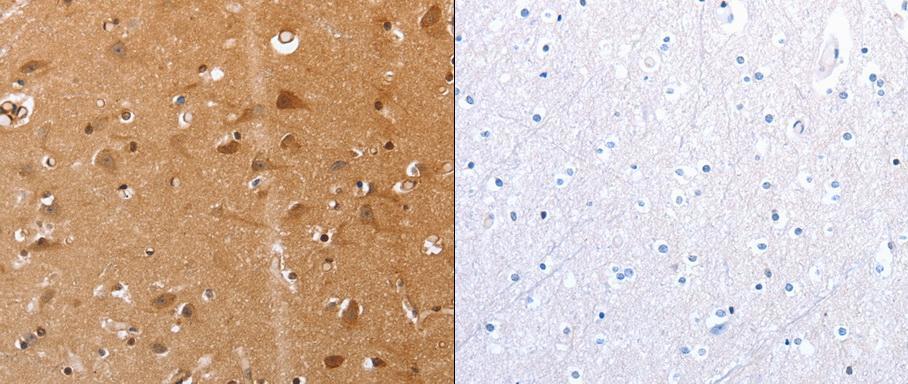

- Predicted cell location: Cytoplasm;Endoplasmic reticulum membrane. Positive control: Human brain and renal cancer tissue . Recommended dilution: 1/25-100 The image on the left is immunohistochemistry of paraffin-embedded human brain tissue using VIMP antibody at dilution 1/20, on the right is treated with the synthetic peptide. (Original magnification:x 200)